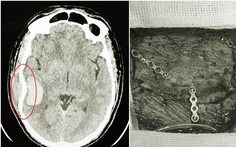

Nhưng bên cạnh đó, một tình huống hi hữu diễn ra trong trận đấu cũng thu hút nhiều sự chú ý. Đó là pha bóng diễn ra ở phút 37, tiền đạo Karim Onisiwo (Mainz) có pha va chạm bằng đầu rất mạnh với Ibrahima Konate (Leipzig).

Hậu quả của pha va chạm là Onisiwo nằm sân trong đau đớn và các nhân viên y tế phải tức tốc vào sân chăm sóc anh.

Dù rơi vào trạng thái nguy hiểm nhưng Onisiwo vẫn tiếp tục thi đấu. Đáng nói hơn, anh chỉ mất 6 phút để ghi bàn rút ngắn tỉ số xuống còn 1-2 cho Mainz.

Thế nhưng mọi chuyện không suôn sẻ như vậy theo tiết lộ từ giám đốc thể thao của Mainz Rouven Schroder sau trận đấu: "Cậu ta không nhớ gì về việc đã ghi bàn trong hiệp 1".

Ngay đầu hiệp 2, Onisiwo được thay ra bởi Mateta. Vụ việc đã gây ra những bất bình về việc chấn thương của các cầu thủ bởi cách đó ít ngày, Jan Vertonghen (Tottenham) trong trận đấu với Ajax ở Champions League cũng gặp chấn thương vùng đầu rất nặng và đã đổ máu.